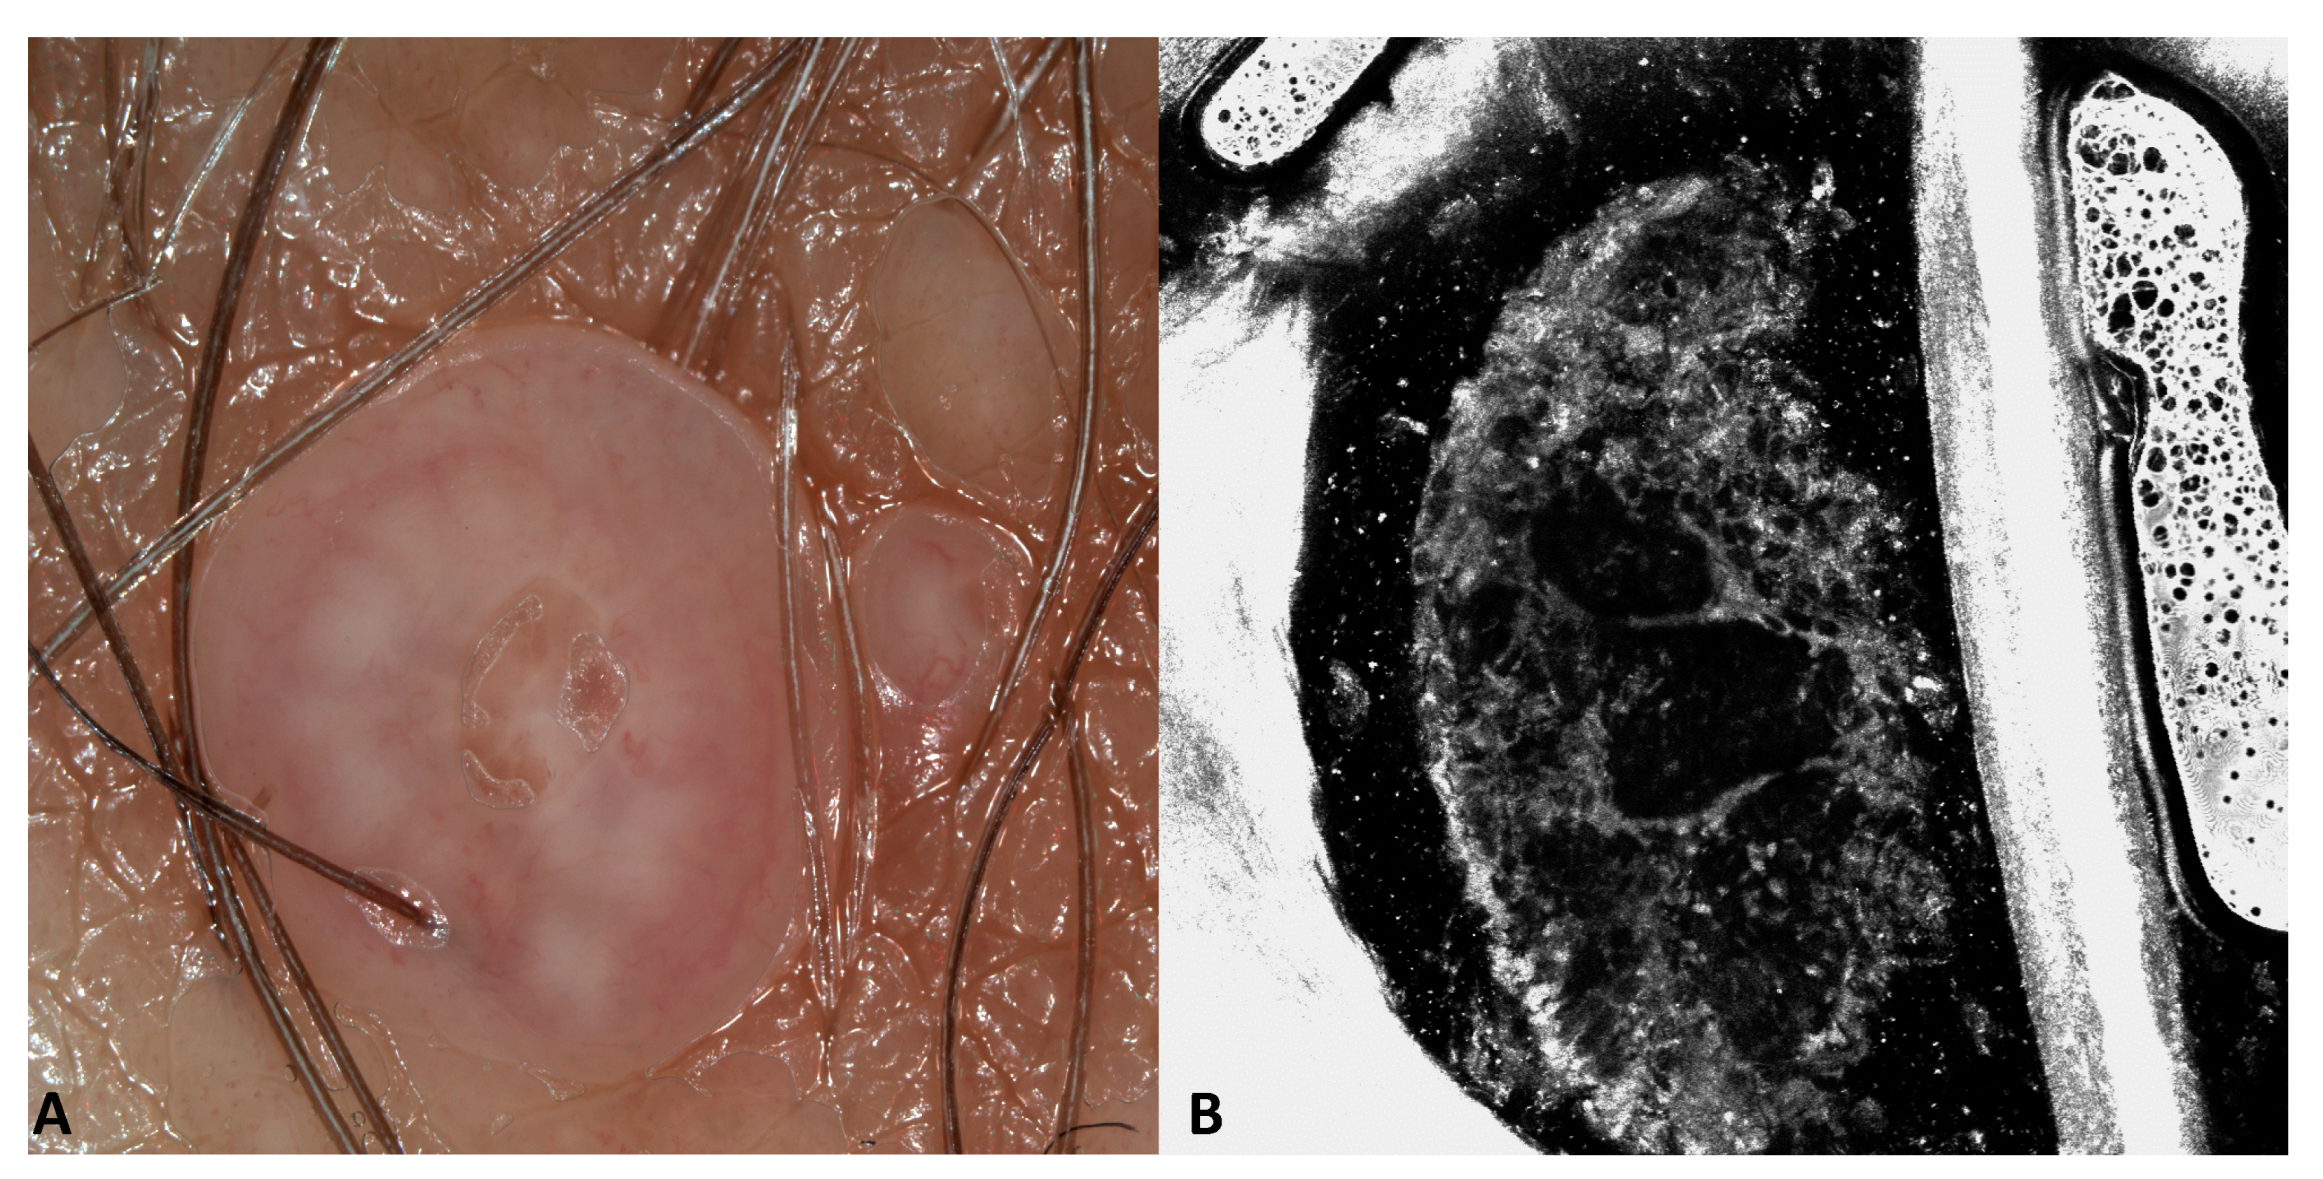

3.2. Images of the Imitators of Genital Warts